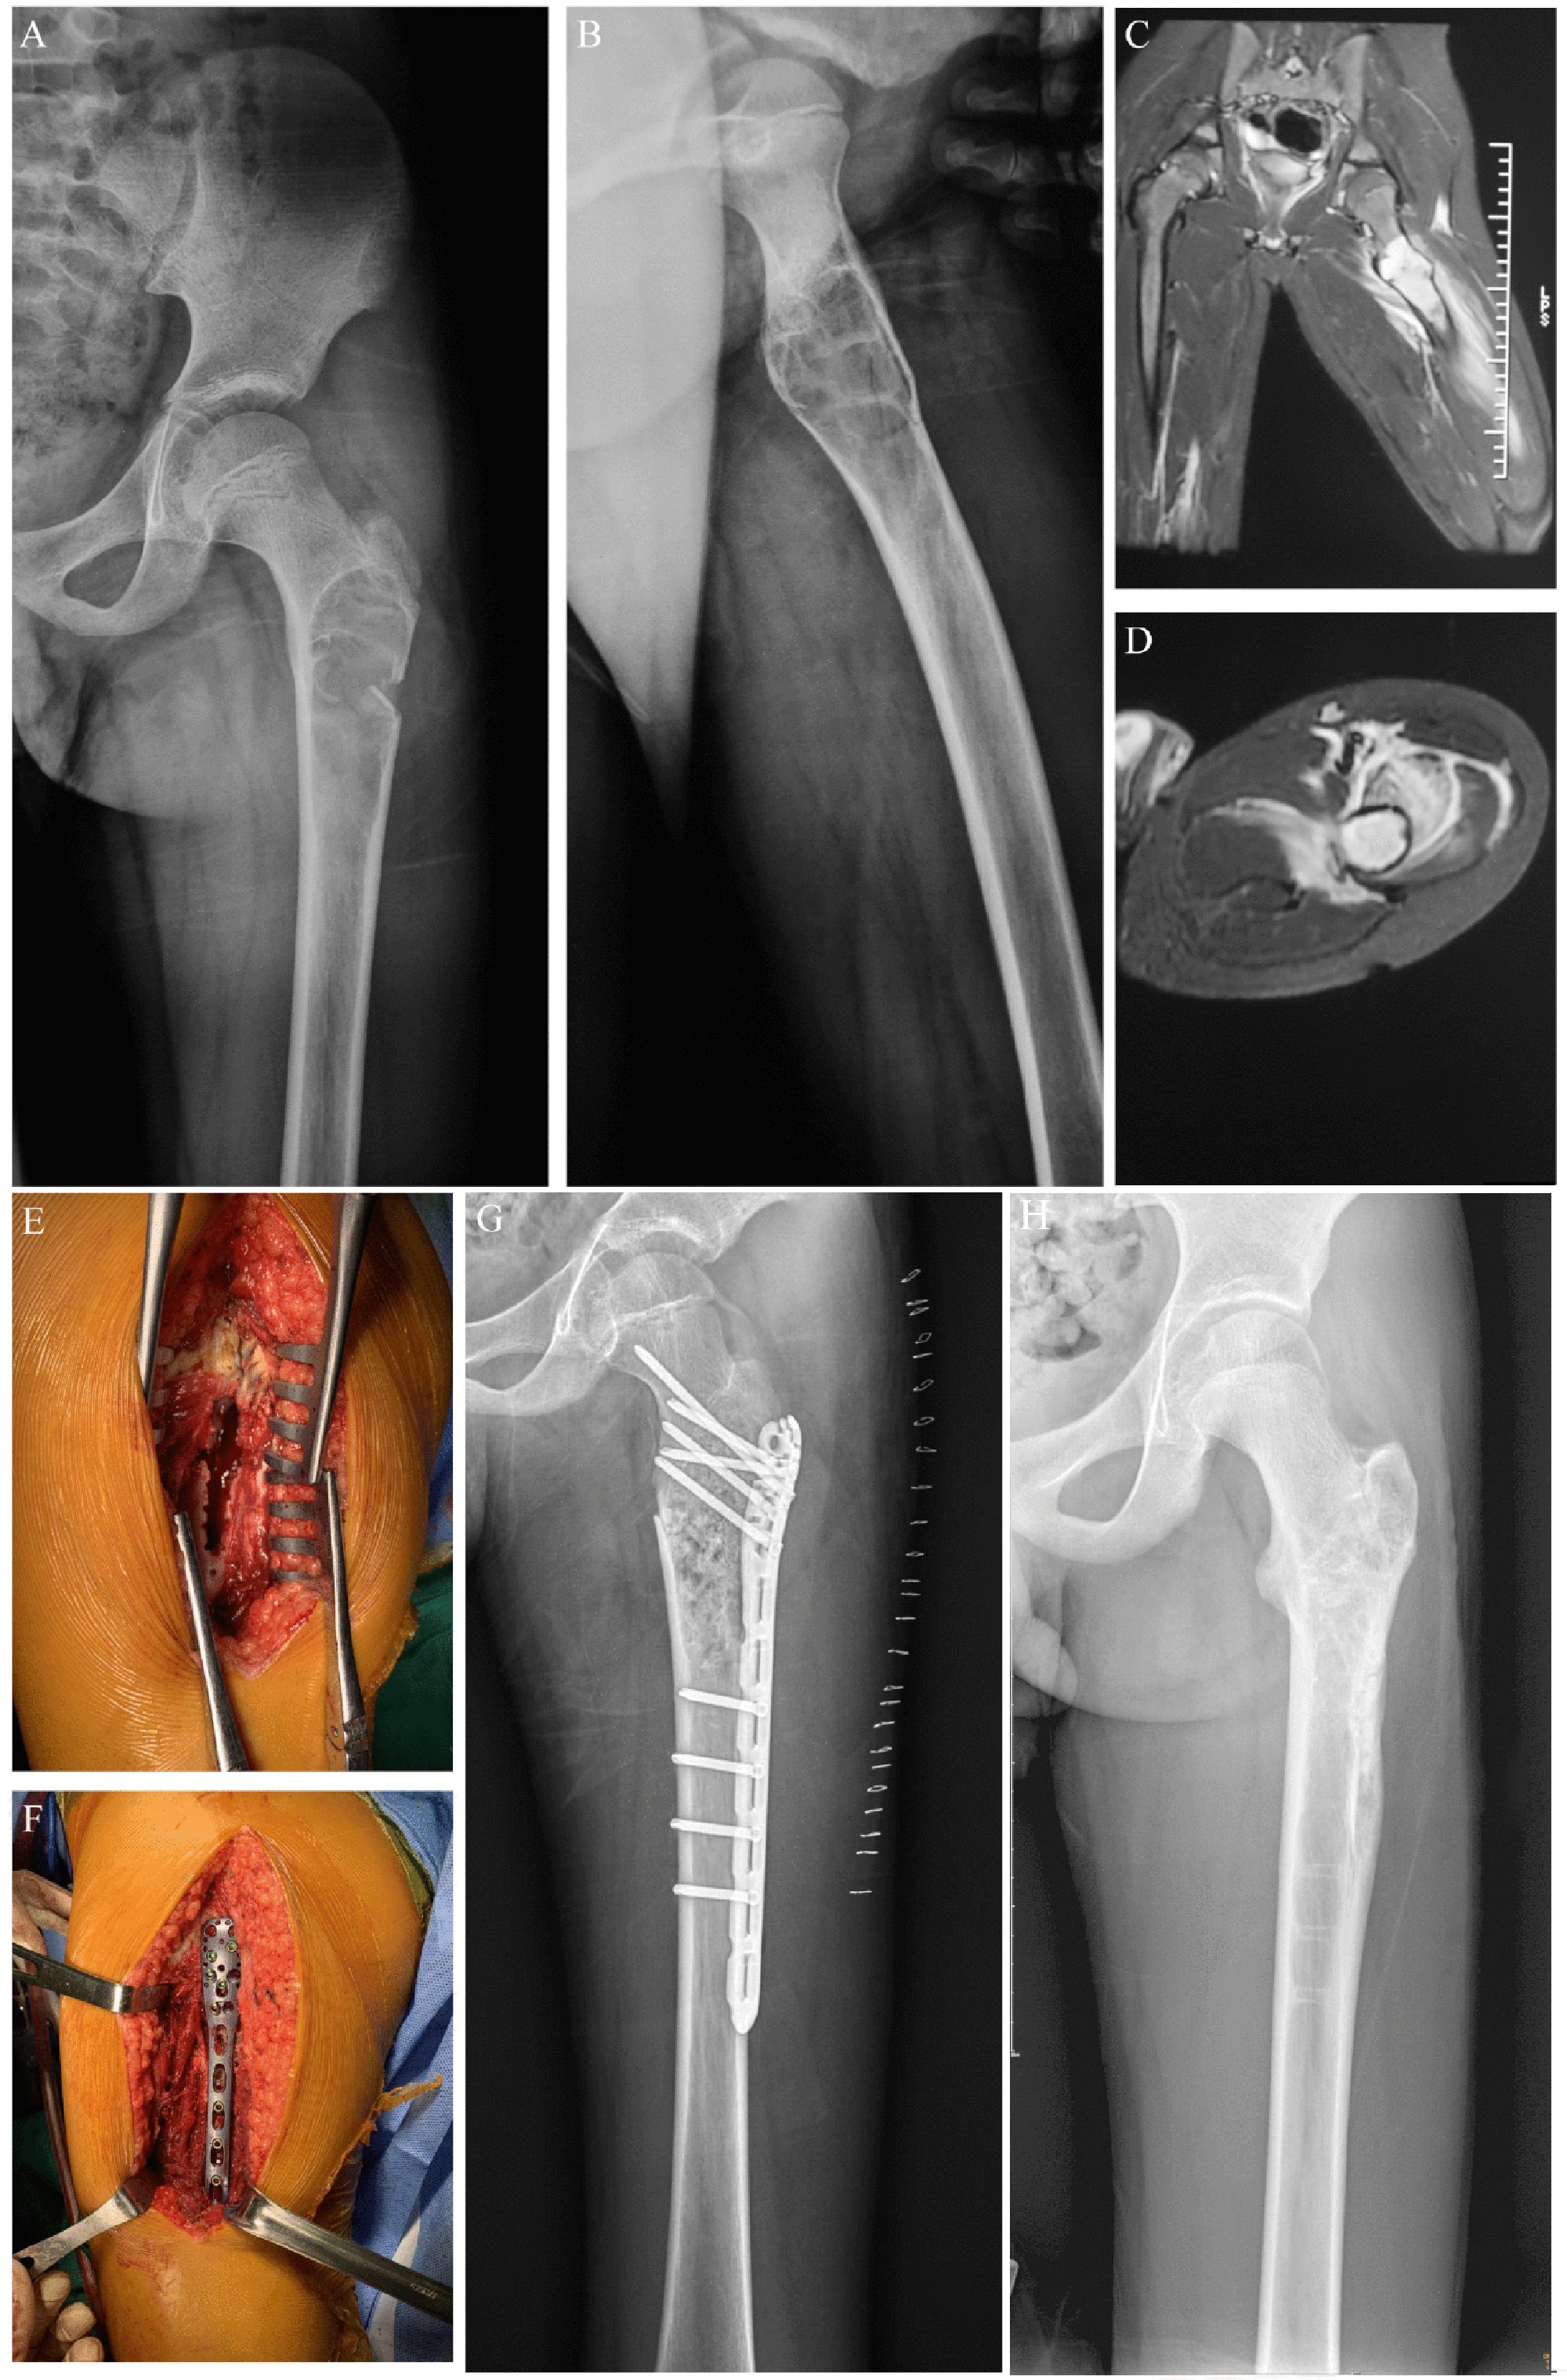

Figure 3. Preoperative, postoperative, and operative images of a pathological fracture of the proximal end of the left femur in an 11-year-old male patient. (A) Preoperative posterior radiographic image of the patient. (B) Preoperative lateral x-ray image of the patient. (C) Preoperative coronal MR image of the patient. (D) Preoperative transverse MR image of the patient. (E) Enlarged cortical window with adequate scraping of the lesion. (F) Bone grafting, internal fixation with a suitable adult 3.5 mm proximal humerus locking plate, and gross fracture reduction. (G) Postoperative x-ray image of the patient. (H) X-ray image of the patient after the removal of the metal plate.